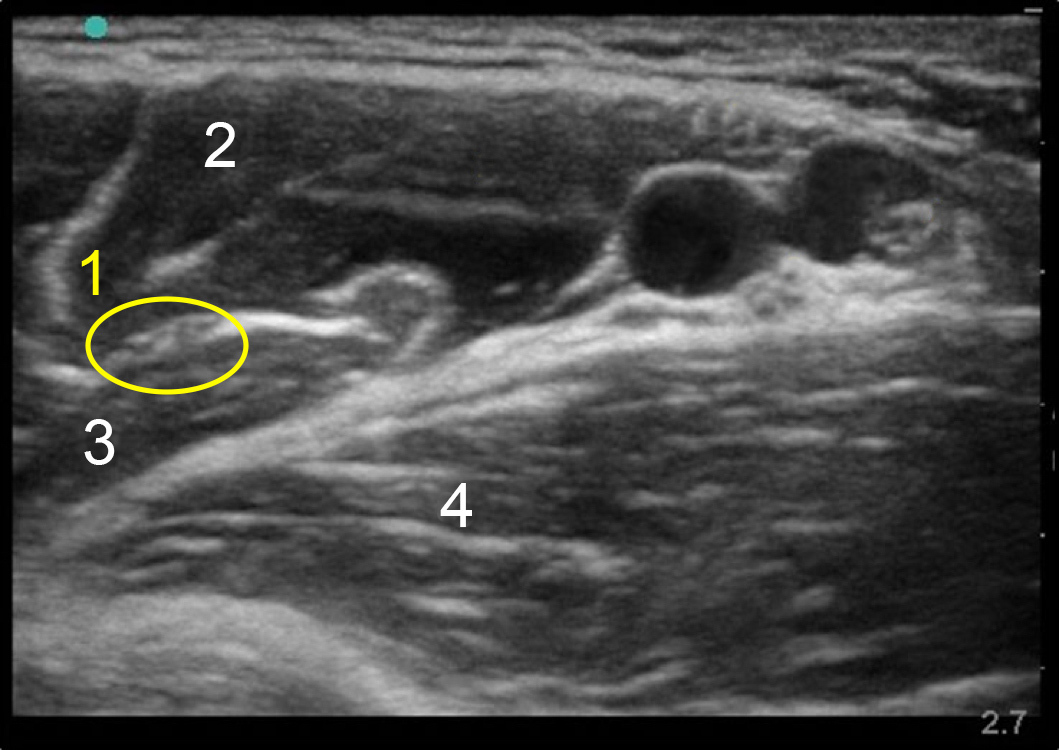

腋肌皮神经图像

肌皮神经

二头肌

啄肱肌

三头肌